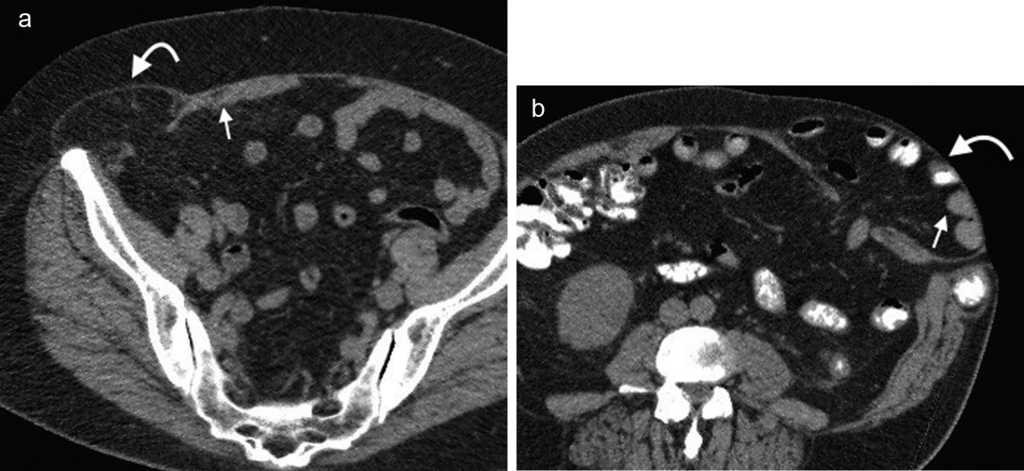

La hernia inguinal indirecta atraviesa el anillo inguinal interno, recorre el conducto y emerge a trav??s del anillo externo, sobresaliendo superior y externamente a los vasos epig??stricos inferiores. Puede extenderse por el conducto esperm??tico o el ligamento redondo hacia el escroto o los labios mayores, respectivamente. Es posible ver el cuello del saco herniario en el anillo inguinal profundo1 (fig. 1). Un hallazgo que ayuda a su caracterizaci??n es el signo del gancho. Este debe su nombre a la forma c??ncava que adopta la arteria epig??strica inferior en el plano axial en su curso proximal, al ser comprimida por una hernia indirecta6.

En lo que respecta a la directa, esta se ubica por encima del ligamento inguinal y medial a los vasos epig??stricos inferiores, y en general es adquirida. Su incidencia aumenta con la edad por el debilitamiento de la fascia transversal en el tri??ngulo Hesselbach1. Suele ser m??s frecuente en hombres y est?? menos asociada a la estrangulaci??n de las asas, posiblemente porque en general no atraviesa todo el curso del canal4 (fig. 2). El contenido del canal inguinal es comprimido lateralmente, mientras que su grasa se ubica como una luna creciente, produciendo el signo de la semiluna creciente (un hallazgo que ayuda a la caracterizaci??n de estas hernias)7.